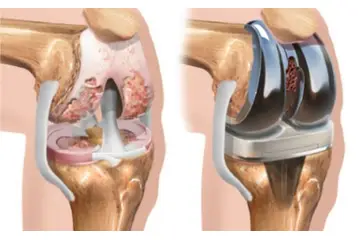

Fibröz kıkırdak, travma veya aşınma sonucu zarar görebilir. Bu tür durumlarda, kıkırdak onarım süreçleri yavaş ilerleyebilir ve genellikle cerrahi müdahale gerektirebilir. Fibröz Kıkırdak Hastalıkları Fibröz kıkırdak ile ilişkili bazı hastalıklar ve durumlar şunlardır:

Bu hastalıkların tedavisi genellikle fizik tedavi, ilaç tedavisi ve cerrahi yöntemleri içerir. Sonuç Fibröz kıkırdak, vücudun destek ve hareket sisteminde kritik bir rol oynamaktadır. Yapı ve fonksiyon özellikleri sayesinde, çeşitli anatomik yapılar içinde önemli işlevler üstlenir. Fibröz kıkırdağın sağlığını korumak, genel fiziksel sağlık açısından önemlidir. Beslenme, egzersiz ve uygun tedavi yöntemleri ile fibröz kıkırdak sağlığı desteklenebilir. Ekstra Bilgiler Fibröz kıkırdağın onarım süreçleri, yaşla beraber yavaşlayabilir. Bu nedenle, yaşlanma sürecinde eklem sağlığını korumak için düzenli egzersiz yapmak ve sağlıklı beslenmek oldukça önemlidir. Ayrıca, fibröz kıkırdak sağlığını korumak için anti-inflamatuar besinlerin tüketilmesi önerilmektedir. Omega-3 yağ asitleri ve antioksidanlar bu bağlamda faydalı olabilir. Fibröz kıkırdak ile ilgili araştırmalar, bu dokunun onarım ve rejenerasyon potansiyelini artırma yönünde devam etmektedir. Gelecekte, biyomühendislik ve hücresel tedavi yöntemleri ile fibröz kıkırdağın onarımını sağlamak mümkün hale gelebilir. |